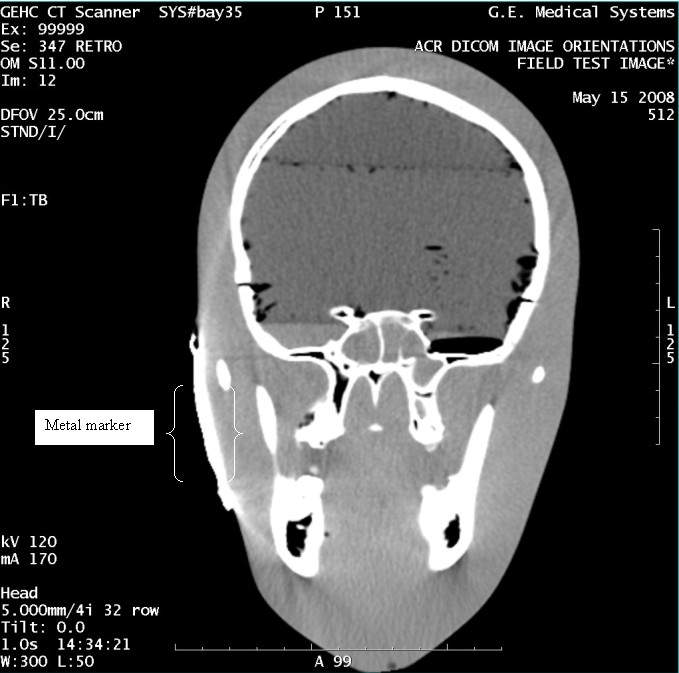

- With the support of the site personnel, examine the images sent

to the Review Station (i.e., 12 series, each with 1 image) and compare

their orientation to the images in this document.

- Each image contains a metal marker on the phantom's right cheek.

- Each image in this document contains a description of the expected

orientation of the metal marker (i.e. to prove Left and Right) as

well as the Posterior and Anterior orientation description.note:

The sample images included in this document use “R”, “L”, “P”, and “A” for “Right”, “Left”, “Posterior” and “Anterior” orientation. The Hospital Review Station may use a different style of annotation. The style used is not relevant to this procedure.

Figure 10. Exam 99999, Series 347